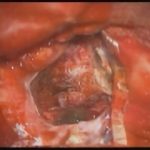

手術前2

摘出 中